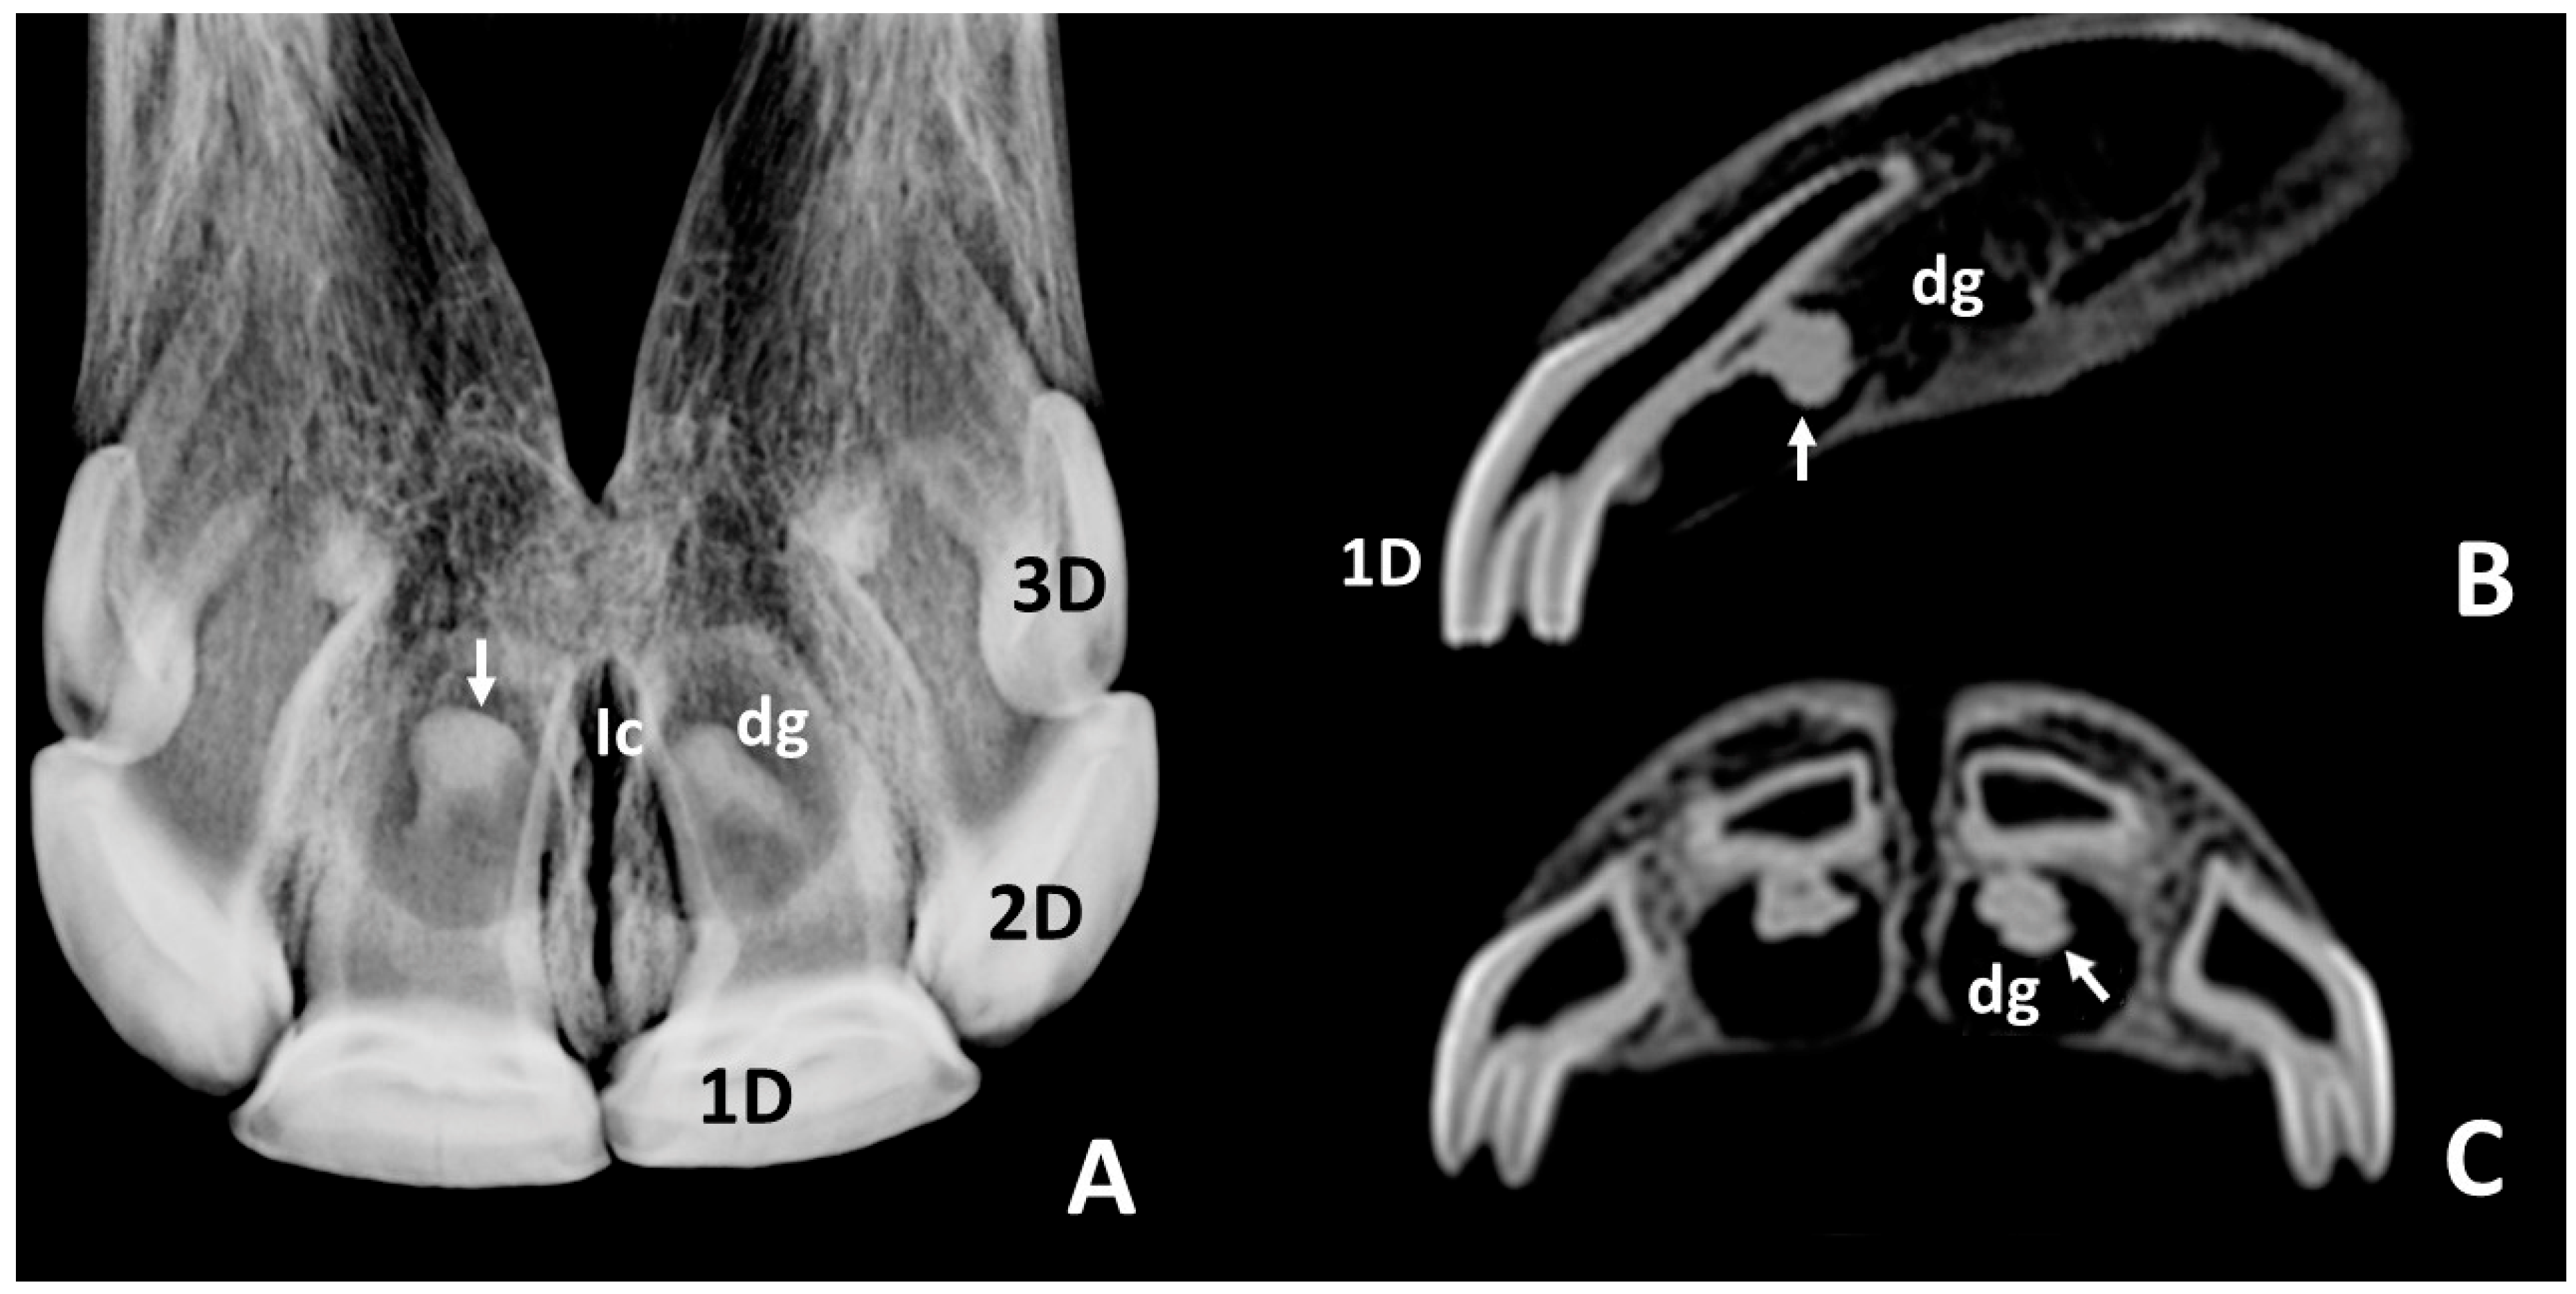

3.2. Radiographic and CT Studies

4.1. Deciduous Incisors: Radiographic and CT Studies

4.2. Permanent Incisors and Alveoli: Radiographic and CT Studies